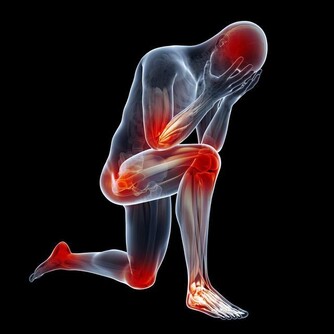

1、憂鬱症 患憂鬱症的人,在吃過香蕉後,感覺好很多。因為香蕉含胺基酸,會轉化成血清促進素,令人放鬆心情、提升情緒。 2、貧血 香蕉鐵質含量高,能刺激血液內的血紅素。 3、高血壓 香蕉含極高量的鉀,但鹽分低,最理想的降血壓食物。最近,美國食品及藥物管理局宣布,允許香蕉業宣傳「香蕉能降低高血壓和中風機率」。 4、腦力 在英國Twickenha就有200名學生,為了要提升腦力,幫助考試,在學期開始,於早餐、午餐和午休時,都吃適量香蕉。研究顯示,含豐富鉀質的香蕉,能提高學生的專注力,對他們讀書有所幫助。 5、便秘 香蕉的纖維質很高,可幫助恢復腸胃正常活動,消除便秘,無需服用清瀉劑。 6、宿醉 香蕉牛奶加蜜糖可以幫助解酒。香蕉放鬆胃部,蜜糖提升血糖平穩,抒緩精神和製造碳水化合物。 7、心絞痛 香蕉對身體有一種天然的制酸性,有鎮痛作用。 8、早上無精打彩 早餐後午飯前,吃少量香蕉可保持血糖平穩。 9、蚊叮蟲咬 用香蕉皮內部輕擦患處,可消腫消炎。 10、緊張 香蕉的維生素B含量高,可幫助抒緩神經系統。 11、體重超重 奧地利心理學學校研究發現,工作壓力大,使員工會不斷進食甜食和零食去抒緩情緒。研究員對5000名醫院的病人做研究,肥胖症狀者,通常都是工作壓力非常大的工作。 研究總結認為,要避免引起對抒緩情緒食物的慾念,就應該約每兩小時吃一點高碳水化合物的食物,以防止身體內的血糖升高。 12、胃潰瘍 香蕉是調理腸胃失調的食方,因為香蕉有著柔軟的纖維而且柔滑。對於長期患者來說,香蕉是唯一可以進食的未煮熟食物,而不會有不良反應。香蕉還可以中和胃酸和減少疼痛。 13、體溫控制 在不同國家、地區和文化中,都有把香蕉作為一種「降溫」的水果,可以用作降低身、心的熱度。在泰國,孕婦為了使嬰兒出生時有較為涼快的環境,臨盆時就會吃香蕉。 14、戒煙 香蕉可以幫助戒煙。香蕉含維生素B6和B12,也含鉀和鎂,可以復元戒煙者,因為沒有了尼古丁刺激的影響。 15、壓力 香蕉所含的鉀,可以調節心跳使之正常化,從而將氧氣順利送到大腦,以及調節身體的水分。當受到壓力緊張時,我們的新陳代謝就會加快,因而使鉀的含量下降。鉀含量高的香蕉,正好作補充。 16、中風 據著名醫學雜誌「The New England Journal of Medicine」的研究指出,長期吃香蕉,中風死亡的機會率大大降低40%。

什麼人不適合吃香蕉? 1:體質偏虛寒者 香蕉性寒體質偏虛寒者最好避之則吉,像胃寒、虛寒、腎炎、也不要吃香蕉,以上幾種病人如果吃香蕉也不利於身體的健康。還有點懷孕期腳腫的患者,也最好是不要吃香蕉。 2:空腹的人 香蕉是可以促進胃腸道蠕動的,如果空腹吃就會造成腸胃的提前工作,長期空腹吃香蕉也不利於身體的健康。為什麼不能空腹吃香蕉呢,因為空腹時腸胃中幾乎沒有可提供消化的食物,在空腹時吃香蕉就會加快腸胃的運動,促進血液的循環,增強心臟的負荷,容易導致心肌梗塞。 3:關節炎患和糖尿病患者 香蕉的含糖量是比較高的,會使血液循環減慢,代謝物堆積,如果關節炎和糖尿病患者不應該吃香蕉,否則會加重病情。 4:腎炎患者 腎炎患者也是不可以吃香蕉的,因為香蕉中含有大量的鉀、鎂元素,腎炎患者的派濾功能比較差,香蕉會使血液中的鈣鉀鎂比例失調,進而促進腎病的加重,所以腎病寒者最好是不要吃香蕉。